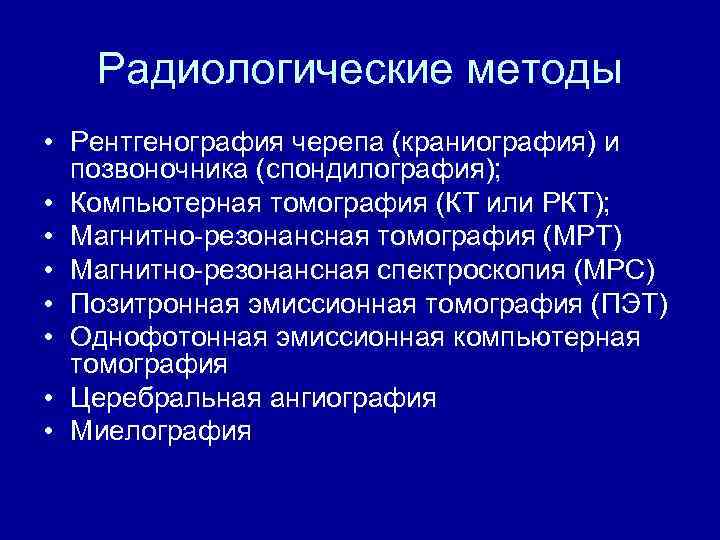

Радиологические методы • Рентгенография черепа (краниография) и позвоночника (спондилография); • Компьютерная томография (КТ или РКТ); • Магнитно-резонансная томография (МРТ) • Магнитно-резонансная спектроскопия (МРС) • Позитронная эмиссионная томография (ПЭТ) • Однофотонная эмиссионная компьютерная томография • Церебральная ангиография • Миелография

Радиологические методы • Рентгенография черепа (краниография) и позвоночника (спондилография); • Компьютерная томография (КТ или РКТ); • Магнитно-резонансная томография (МРТ) • Магнитно-резонансная спектроскопия (МРС) • Позитронная эмиссионная томография (ПЭТ) • Однофотонная эмиссионная компьютерная томография • Церебральная ангиография • Миелография